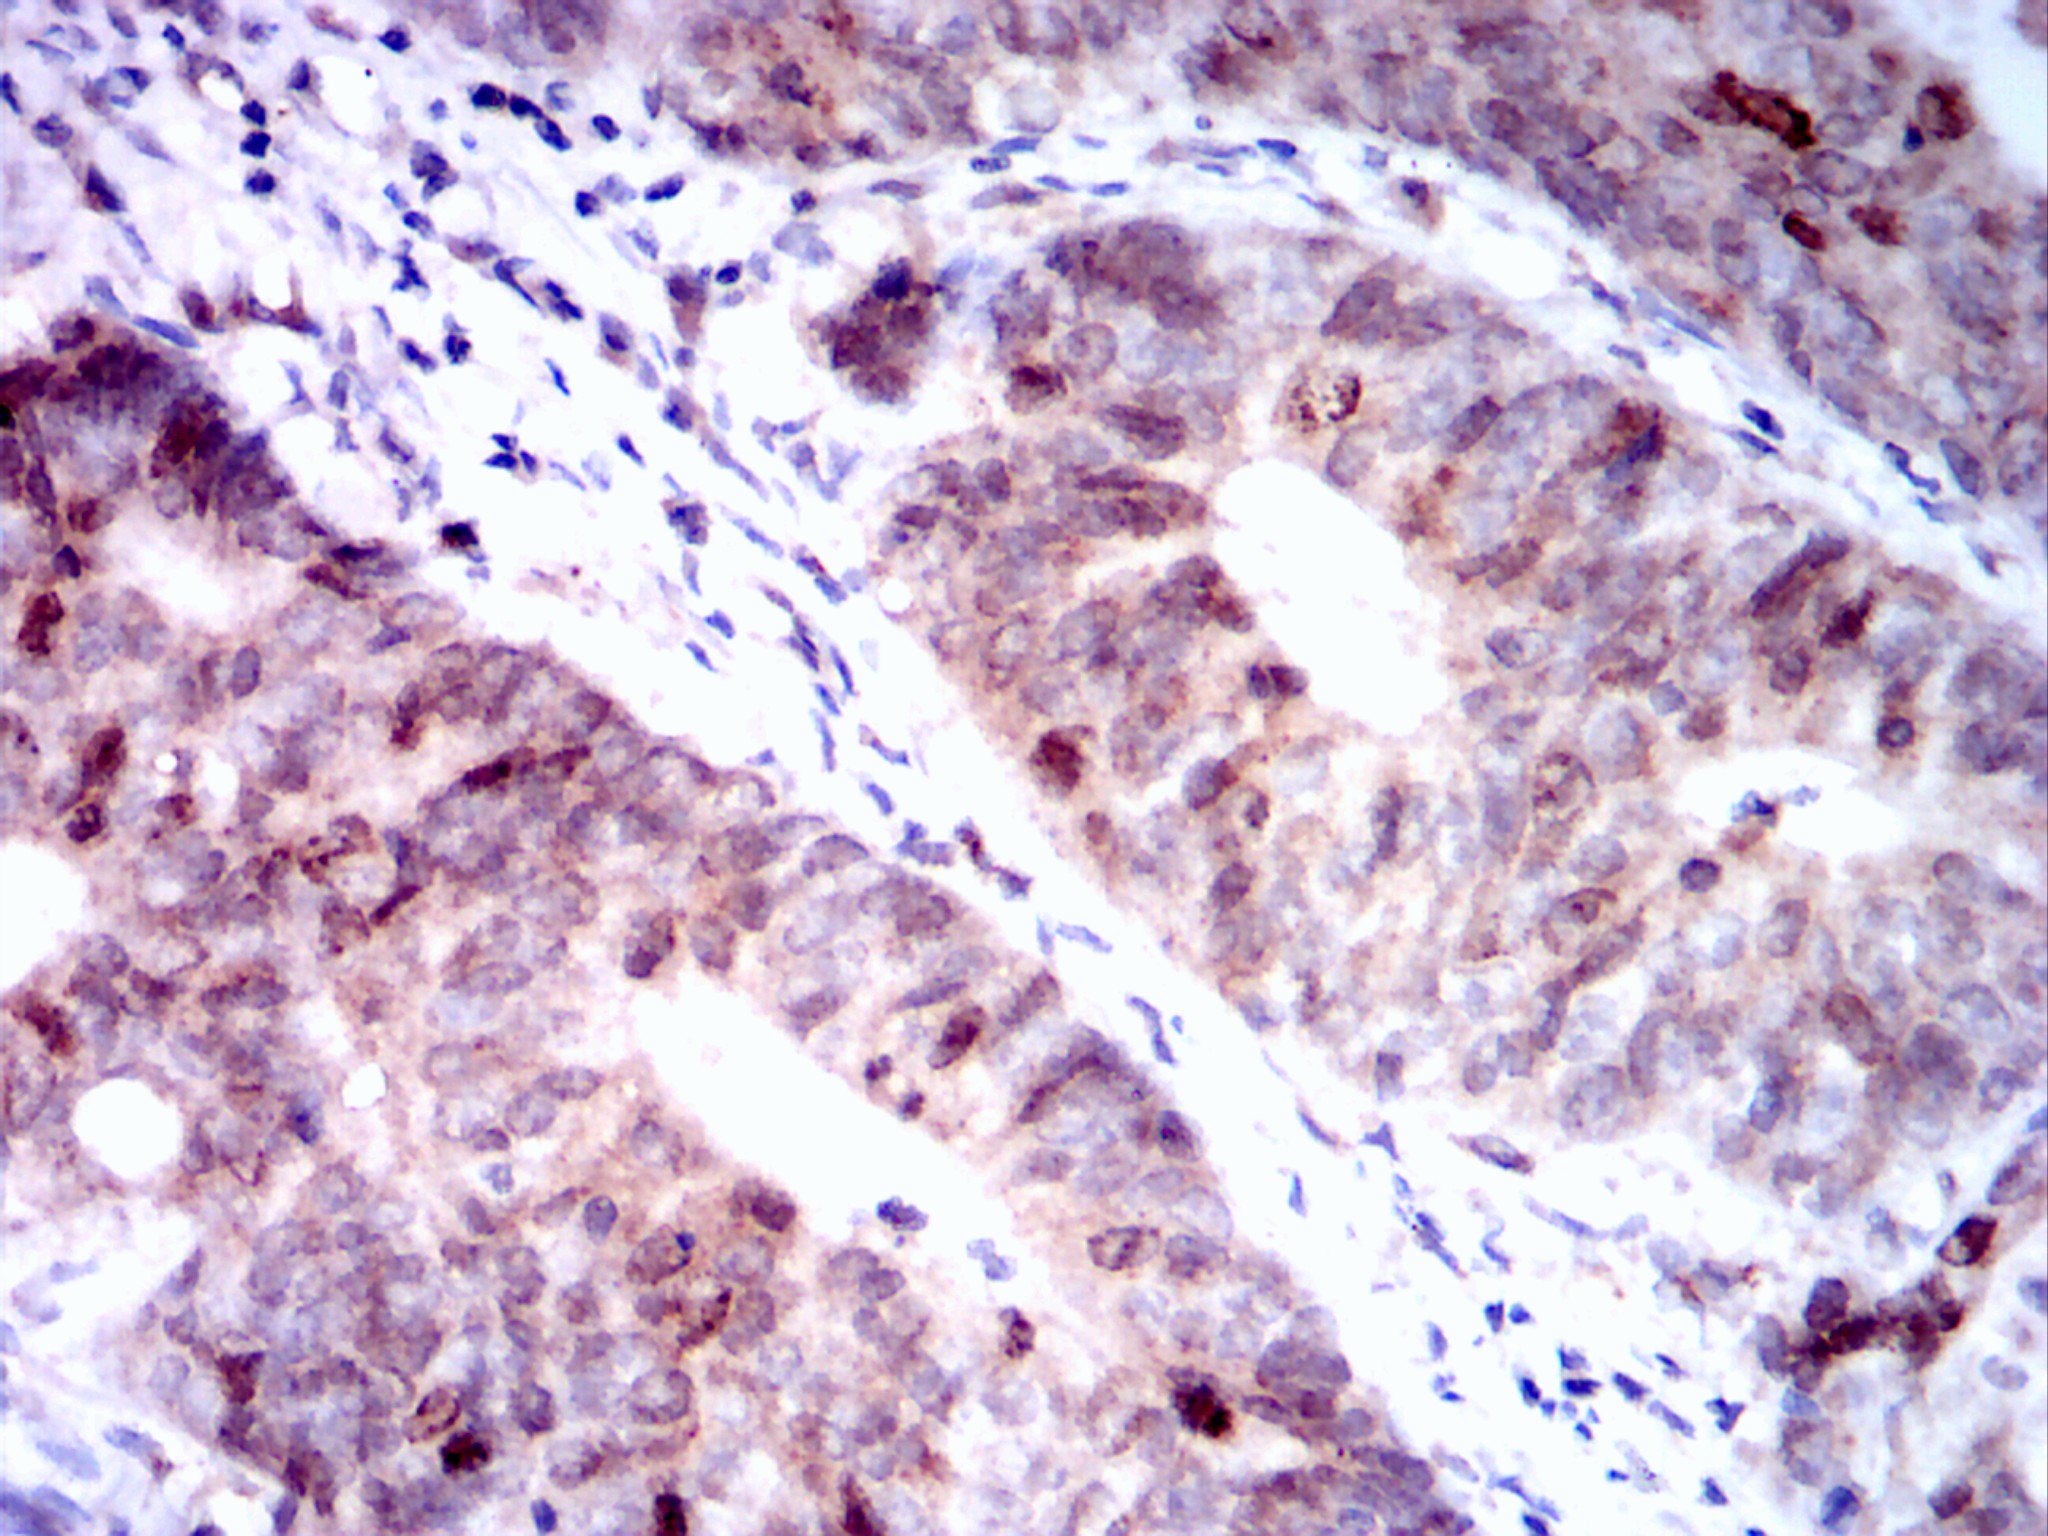

分类: 科研抗体货号: 20093别名: PVALB; MGC13548; MB应用: IHC反应种属: Human